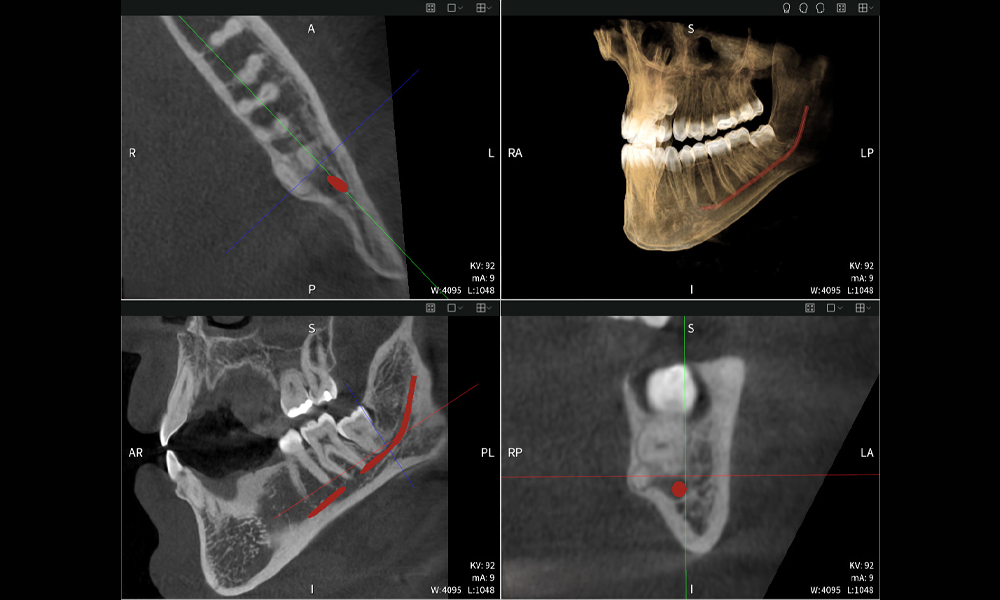

Below you will find a case from Dr. med. dent. Oliver A. Centrella, in which the CBCT images obtained with Seethrough Max provided crucial information on the complex anatomy and the critical relationship between the wisdom teeth and the inferior alveolar nerve. In this case, there is a indication for the surgical removal of the wisdom teeth.

Figures b–d show various views of a 3D reconstruction of the mandible, providing a comprehensive overview of the mandibular anatomy, the position of the nerves in relation to the teeth, and allowing assessment of tooth symmetry and alignment.

Figure d shows the previously treated tooth 48, with its crown removed, and its roots left in proximity to the nerve, illustrating the high risk of nerve damage.